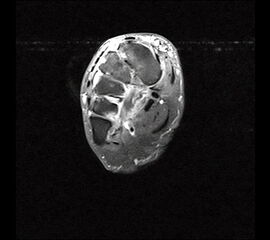

Ruptur der Peronaeus longus Sehne mit proximalisiertem Sehnenstumpf im MRT

Abbildung 14

Die akute vollständige Ruptur betrifft in der Mehrzahl der Fälle die Peronaeus longus Sehne, typischerweise in Höhe des Kuboid-Tunnels 40. Die Patienten berichten über ein geräuschvolles Reißen der Sehne mit anschließenden Schmerzen am lateralen Fußrand. Klinisch besteht eine Schwellung und Druckschmerzhaftigkeit im Sehnenverlauf. Die Plantarflexion und die Eversion des Fußes gegen Widerstand ist schmerzhaft 41. Bei einer kompletten Ruptur der Peronaeus longus Sehne kann es zu einem Ausriss des Os peronaeum kommen, dieses kann bis in Höhe des Außenknöchels dislozieren. Zur Beurteilung der Sehne ist das MRT mit Kontrastmittel das Verfahren der ersten Wahl.